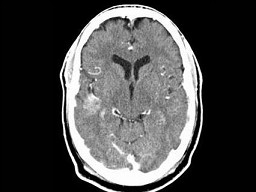

男,54岁,癫痫发作,结合图像,最可能的诊断是()

A.脑脓肿

B.脑出血

C.海绵状血管瘤

D.胶样囊肿

E.脑转移瘤

男,54岁,癫痫发作,请结合影像图像选择最可能的诊断()<img border="0" style="width: 256px; height: 284px;&qu

[单选题]男,54岁,癫痫发作,请结合影像图像选择最可能的诊断()A.脑脓肿B.脑出血C.海绵状血管瘤D.胶样囊肿E.脑转移瘤